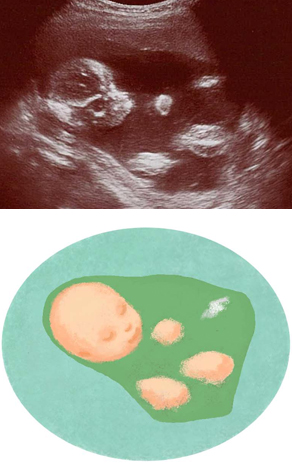

妊娠19週ころの超音波写真

全身が写るのは18~19週ごろまで

上あごの骨が成長し、白く鮮明に確認できました。へその緒や体の一部も見えますが、断面なので丸く写ります。体格が大きくなり、超音波で全身が写るのは18~19週ごろまで。